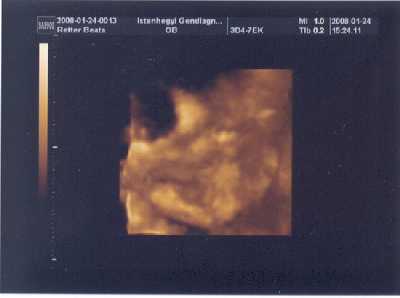

Mi tegnap voltunk a 18. heti genetikai uh-n. Hát lányok, vegyes érzelmek vannak bennem azóta.

Szóval, aminek nagyon-nagyon örülünk, hogy úgy tűnik 2 kiscsajszink lesz!

Az egyikőjük tuti, a másik meg nagy valószínűség szerint, hiszen fiúra utaló jel nincsen! Méretre majdnem egyformák, koruknak is megfelelőek. Minden szervük rendben van! Elég nagy volt a ramazuri bent, a doktornő alig tudta őket vizsgálni, annyira elevenek voltak, még egymást is piszkálták!

De, ami kicsit sokkolt bennünket

, az az hogy az egyik kislányunk a bal lábát néha befelé rotált állapotban tartotta. Először az orvos azt mondta nem tudja hogy a csont ilyen-e (donga láb), vagy csak neki így kényelmes. Vizsgálgatta, aztán mondta, hogy amikor mozog, rúg, akkor fordítja a másik irányba is. Szóval azt mondja, szerinte semmi gond! De a bogarat beleültette a fülünkbe, és azért aggódunk nehogy mégis legyen valami. A párom teljesen lesápadt, én meg magamban aggódom.

Úgyhogy hétfőn fel is hívom a saját dokinkat, hogy nézze már meg ő is, lát-e ilyesmit!

Teszek fel képet, bár annyira a másodikról nem sikerült, mert egyszerűen nem akarta mutatni magát :